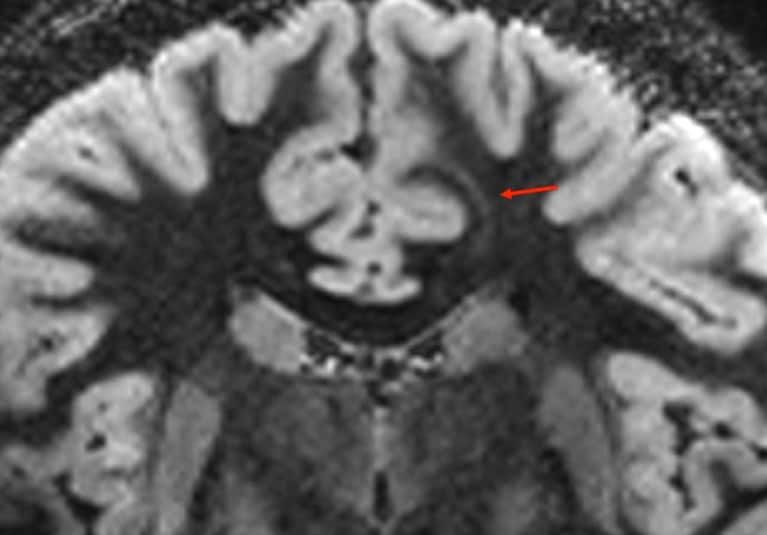

Positron emission tomography scan demonstrates hypometabolism (red arrow) at the site of a suspected left frontal lobe lesion.